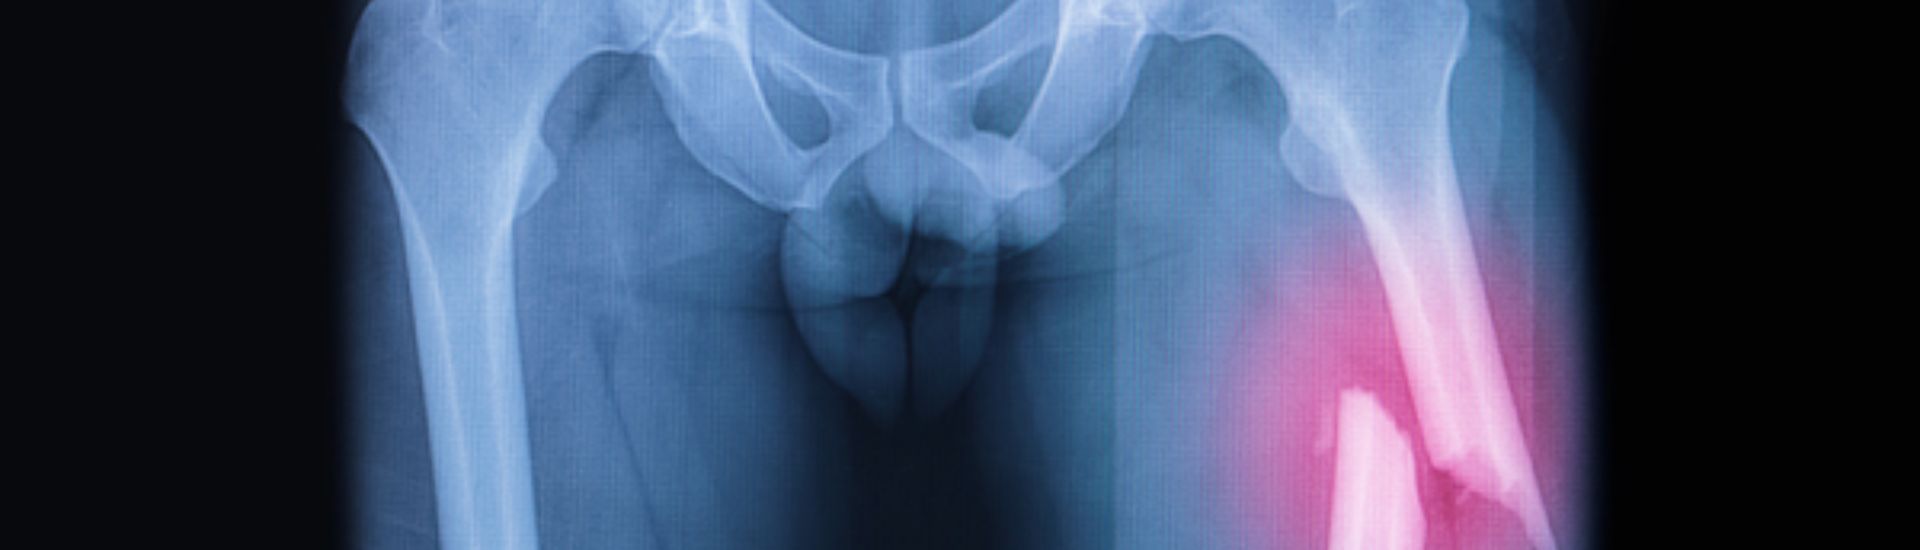

L’Esame RX Femore è una radiografia mirata all’anca e al femore, utilizzata per valutare in modo chiaro e dettagliato l’anatomia e le condizioni di queste strutture. Durante l’esame, vengono utilizzati i raggi X per produrre immagini che permettono di identificare fratture, artrosi, necrosi e altre condizioni patologiche dell’osso e delle articolazioni. Grazie alla sua capacità di fornire immagini ad alta risoluzione, questo esame rappresenta un alleato indispensabile per i medici nella formulazione di diagnosi precise e piani di trattamento personalizzati.

• Fratture dell’anca e del femore: L’esame evidenzia fratture recenti o fratture da stress.

Queste immagini consentono di avere una visione dettagliata delle strutture ossee, aiutando i medici a rilevare anche minime alterazioni e a programmare il trattamento più idoneo.